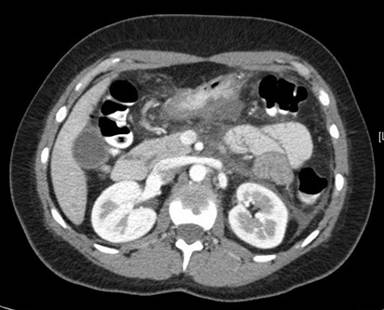

An ultrasound of the right upper quadrant was unremarkable, without evidence of cholelithiasis. Abdominal computed tomography (CT) scan revealed significant inflammatory changes including peripancreatic fluid and fat stranding that extended into the pericolic gutter as well as thickening of the posterior gastric wall, left perinephric stranding, and periportal edema with normal pancreatic anatomy. Magnetic resonance cholangiopancreatography (MRCP) performed two days after admission revealed similar peri-pancreatic inflammatory changes and normal pancreatic anatomy. There was no evidence of gallstone or sphincter dysfunction. The changes discussed above are represented in Figures 1, 2, and 3.

Figure 3. Normal junction of pancreatic duct and common bile duct is seen in this CT image. |